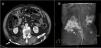

Calcinosis cutis en paciente adulto con dermatomiositis

Calcinosis cutis in adult patient with dermatomyositis